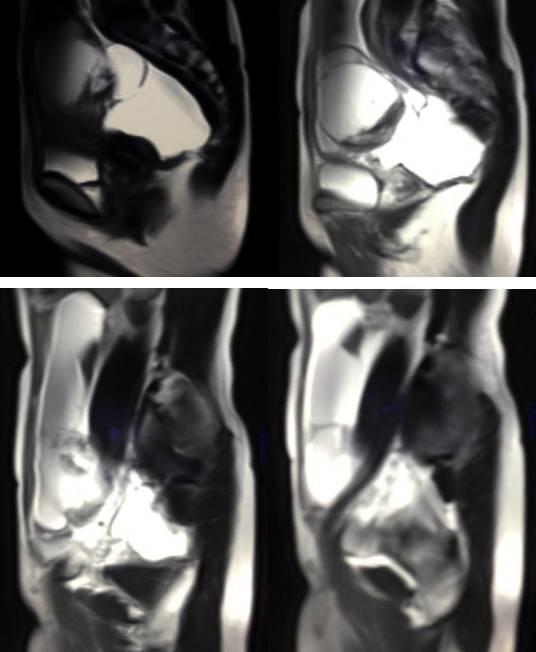

MR检查:

病理结果:黄体血肿

黄体血肿早期:囊内出血较多时,表现为卵巢内近圆形囊肿,囊壁厚,内壁粗糙。

黄体血肿中期:黄体血肿内血液凝固,部分吸收,囊壁变薄而,内壁光滑。

黄体血肿晚期:血液吸收后囊肿变小,转变为白体,内部回声呈实性稍高回

声,与周围卵巢组织分界不清,面靠彩超显示其周围环状血流判断,当血液完全吸收后形成黄体囊肿,囊壁变得光滑,与卵巢其他囊肿难以区分。

根据时间不同MR信号也有所不同,TIWI脂肪抑制序列可以鉴别脂肪和出血。